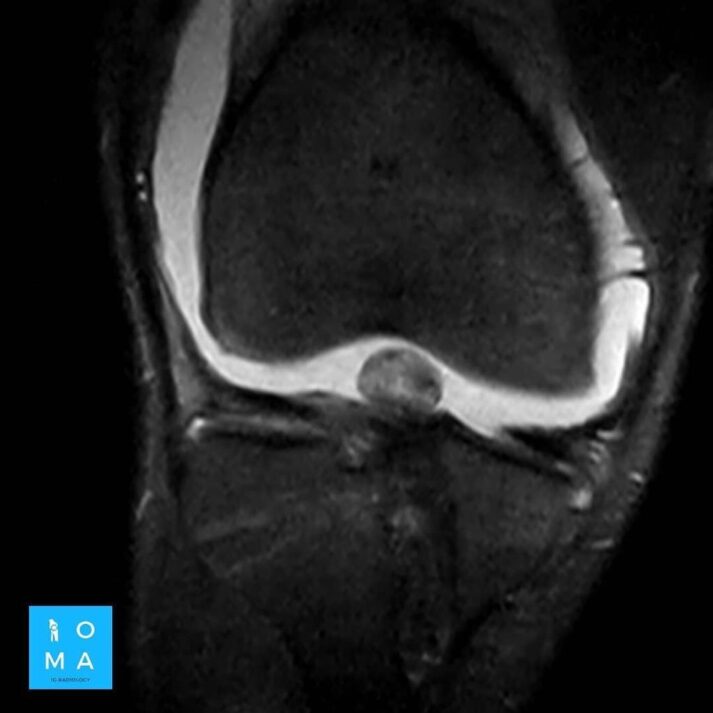

En la evaluación con medio de contraste, se evalúa la relación arterial y de las venas, esto puede servir para buscar la arteria central relacionada con la hiperplasia nodular focal o bien, para evaluar la relación con las estructuras vasculares que son muy importantes para el planeamiento quirúrgico .

en este caso, aún cuando los hallazgos son atípicos tanto para hiperplasia nodular focal como para adenoma, nos inclinamos hacia el diagnóstico de adenoma debido a los antecedentes de la paciente, el tamaño de la lesión, el área de sangrado, el contenido de grasa.